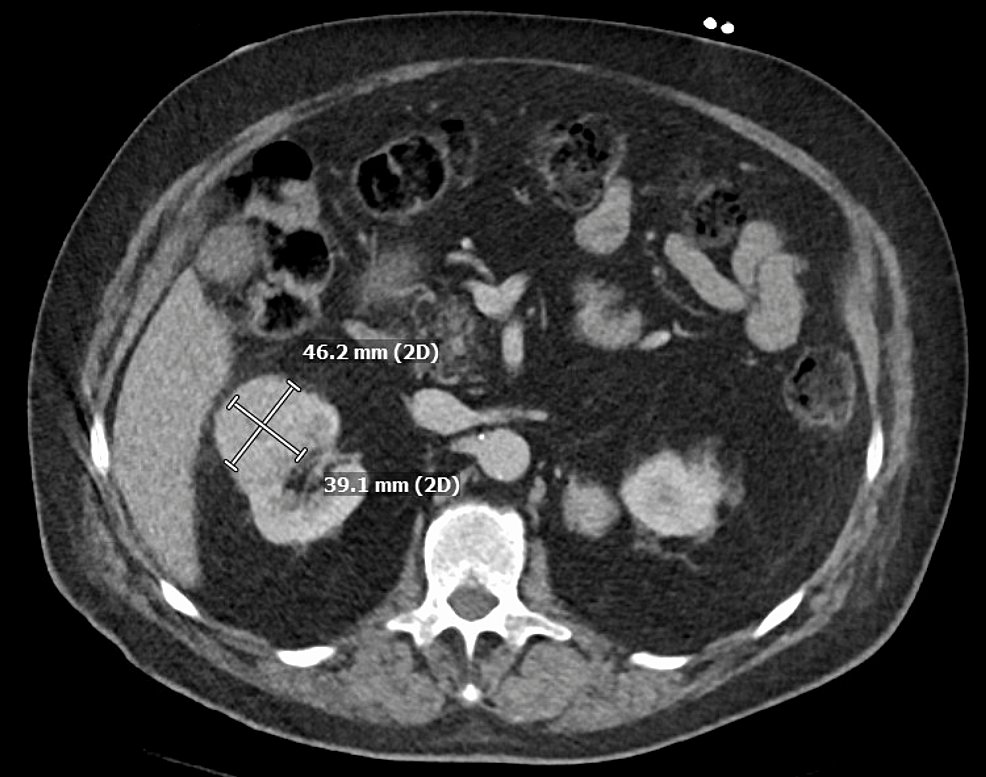

Case Report Renal Tumor . Low grade oncocytic renal tumor: Primary renal collision tumors are rare, and there have been few reports of them. Here, we report a case of renal collision tumor composed of a clear cell renal cell carcinoma (ccrcc) and a ccprct. Renal cell carcinoma (rcc) is the most common renal tumor, with lung, bone, and liver being the primary sites of metastasis. Renal cell carcinoma (rcc) is one of the most common malignancies worldwide with nearly 81,000 new cases and 15,000 deaths. The study was conducted a case of giant renal cell carcinoma who required surgical resection of the tumor at hasan sadikin general. Discussion based on naming conventions and biological behavior, the author who identified the first case of this type of tumor named it. Here, we report a case of metastatic renal cell carcinoma that was successfully treated with deferred cytoreductive nephrectomy following lenvatinib plus. To the best of our knowledge

Low grade oncocytic renal tumor: To the best of our knowledge Primary renal collision tumors are rare, and there have been few reports of them. Renal cell carcinoma (rcc) is the most common renal tumor, with lung, bone, and liver being the primary sites of metastasis. Discussion based on naming conventions and biological behavior, the author who identified the first case of this type of tumor named it. Renal cell carcinoma (rcc) is one of the most common malignancies worldwide with nearly 81,000 new cases and 15,000 deaths. The study was conducted a case of giant renal cell carcinoma who required surgical resection of the tumor at hasan sadikin general. Here, we report a case of renal collision tumor composed of a clear cell renal cell carcinoma (ccrcc) and a ccprct. Here, we report a case of metastatic renal cell carcinoma that was successfully treated with deferred cytoreductive nephrectomy following lenvatinib plus.

Case Report Renal Tumor Renal cell carcinoma (rcc) is one of the most common malignancies worldwide with nearly 81,000 new cases and 15,000 deaths. The study was conducted a case of giant renal cell carcinoma who required surgical resection of the tumor at hasan sadikin general. To the best of our knowledge Low grade oncocytic renal tumor: Here, we report a case of renal collision tumor composed of a clear cell renal cell carcinoma (ccrcc) and a ccprct. Discussion based on naming conventions and biological behavior, the author who identified the first case of this type of tumor named it. Renal cell carcinoma (rcc) is the most common renal tumor, with lung, bone, and liver being the primary sites of metastasis. Here, we report a case of metastatic renal cell carcinoma that was successfully treated with deferred cytoreductive nephrectomy following lenvatinib plus. Renal cell carcinoma (rcc) is one of the most common malignancies worldwide with nearly 81,000 new cases and 15,000 deaths. Primary renal collision tumors are rare, and there have been few reports of them.